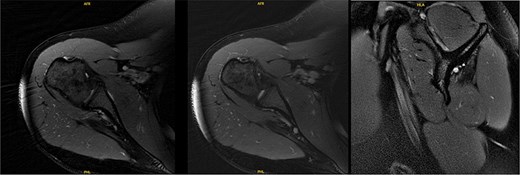

At 9.5 years, she presented reporting recurrent, progressive shoulder weakness and pain during external rotation during self-directed physiotherapy. There was visible atrophy of the right infraspinatus (Fig. 4). She had full symmetrical shoulder range of motion, with 4/5 strength of the right infraspinatus and a markedly weak Hornblower’s test.

Nine and half years after decompression, the patient presented with palpable and visible atrophy of the right infraspinatus.

New MRI arthrogram demonstrated no evidence of new or worsening SSN compression or other pathology. Imaging demonstrated increased right infraspinatus muscular tissue (Fig. 5), however, with significant continued fatty infiltration and persistent atrophy compared to the contralateral side.

MRI at 9.5 years after decompression demonstrated increased right infraspinatus muscular tissue.